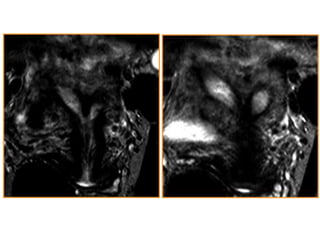

RMN

 Poseee una precisión cercana al 100% en el

estudio de las anomalías müllerianas

 Delimita con fiabilidad la anatomía uterina interna

y externa

 Permite un estudio multiplano

 Posibilita diagnósticos alternativos

 Es considerada la técnica de elección